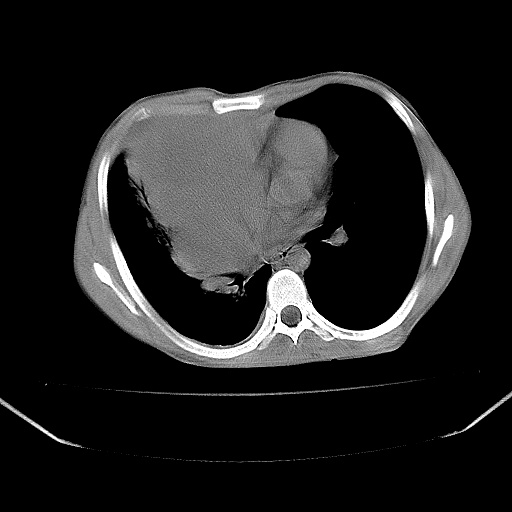

以下是引用zjzjr在2008-7-20 12:57:00的发言:[br]考虑为生殖源性肿瘤(内胚窦瘤),侵袭性胸腺瘤可能性大;右侧少量胸腔积液。

以下是引用xinliheng001在2008-7-20 21:17:00的发言:[br]右纵隔巨大分叶状软组织均质密度肿块,右上肺叶受压明显,纵隔右移、胸膜受累有少量积液和结节样增厚。应增强扫描一定会有更具诊断价值的信息。

以下是引用xinliheng001在2008-7-20 21:17:00的发言:[br]右纵隔巨大分叶状软组织均质密度肿块,右上肺叶受压明显,纵隔右移、胸膜受累有少量积液和结节样增厚。应增强扫描一定会有更具诊断价值的信息。